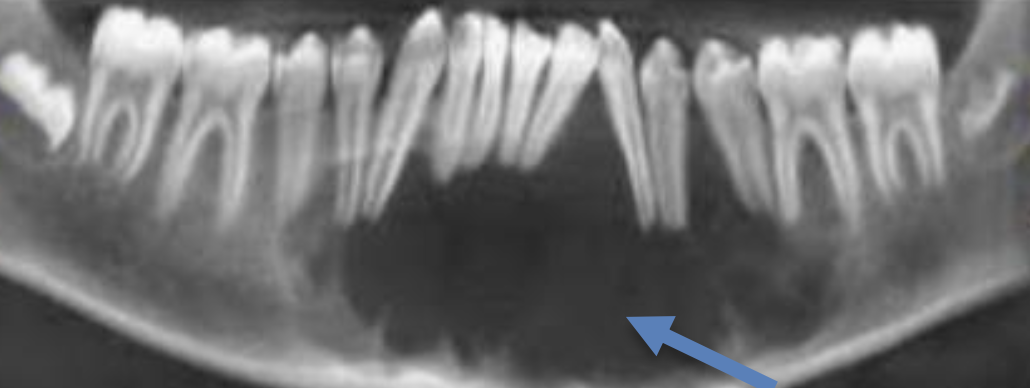

| Odontogenic Keratocyst cyst (OKC) |

下顎骨後端,下齒槽管上方 | 10-40y | 組生齒(40%) | |

| Radiolucent、 MD方向下顎骨吸收,但牙根完整。  |

|||||

| 4-8 層、副角化(有核)、Basal cell 為 palisaded(柵狀) | |||||

| 高復發 (30%) | |||||

Gorlin syndrome

- SUFU 也可能造成